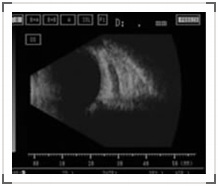

颈动脉-海绵窦瘘是颈动脉与海绵窦间出现异常沟通,高压动脉血通过瘘口进入海绵窦,导致后者压力增高,影响眼部静脉血回流。根据病因可分为外伤性(高流瘘)和自发性(低流瘘)。患者常自述可闻及吹风样杂音,表现为眼球突出,眼睑及结膜肿胀,结膜血管螺旋状扩张、色鲜红,眼球运动受限,眶区听及血管杂音。B超显示眼上静脉扩张,多条眼外肌肥厚。CT除以上表现外,还可发现海绵窦增宽。治疗方法为经股动脉或眼上静脉插管,可脱球囊栓塞瘘口。自发性低流瘘不引起临床症状者可不予治疗。(如图,B超下可见扩张的眼上静脉)。